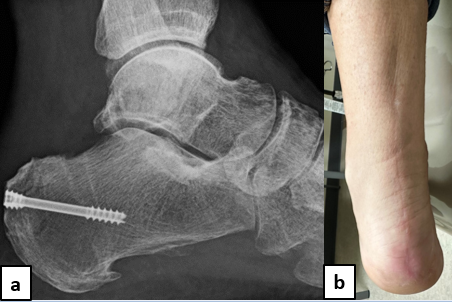

The next step involves calcaneus preparation for the Achilles bone-tendon allograft (Figure 5). There is no consensus in the literature on exact parameters to size the allograft, but it should be large enough to accept a screw. We took the same steps in preparation of remodeling the allograft to anatomically fit the trough created in the calcaneus (Figure 6). After attaining adequate fit of allograft into calcaneus, we permanently fixated the allograft with a headless screw (Figure 7). Holding the foot slightly plantarflexed, we then measured the defect (Figure 8a) and remodeled the Achilles tendon portion of the allograft to the appropriate length (Figure 8c). While performing an anastomosis of the allograft to the native proximal Achilles tendon, the foot should be in a slightly plantarflexed position, knowing that tension will decrease over time.

This case report details the surgical procedure performed for a patient suffering from chronic underlying retrocalcaneal exostosis pathology. This patient subsequently developed an Achilles tendon rupture with initial misdiagnosis. The technique described allows the surgeon to restore the Achilles tendon while augmenting the strength of repair with subsequent FHL transfer, avoids donor site morbidity, and addresses the weakness of the posterior musculature group. We find this technique especially advantageous for chronic Achilles ruptures involving a substantial portion of the distal tendon segment, and we add internal fixation to help stabilize the allograft bone for incorporation into recipient bone.

At final follow-up, the patient treated with this surgical technique was ambulatory in regular shoe gear without the need for any bracing. There was no loss in muscle strength and no noted complications to date with the procedure. One may consider this surgical technique in other patients suffering from retrocalcaneal exostosis pathology and subsequent development of a chronic Achilles tendon rupture, or in patients with extensive distal tendon calcification that leaves no viable tendon after debridement.